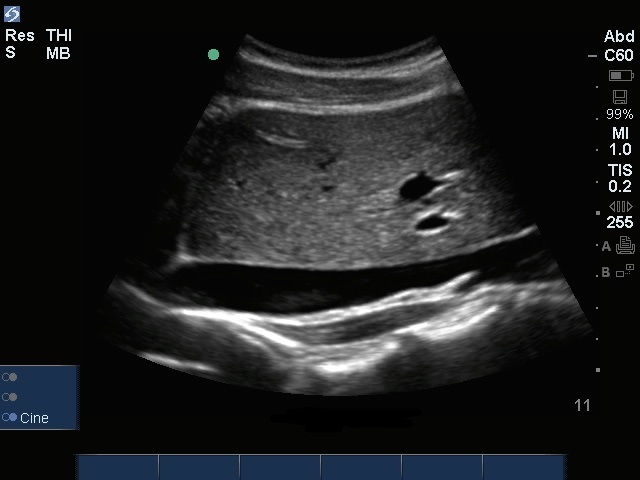

下腔静脉 (IVC) 矢状面图